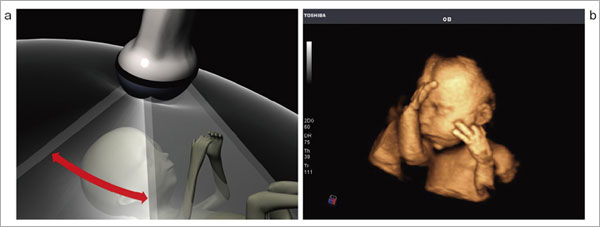

それらの課題を克服するソリューションとして,振動子が機械的に揺動制御可能な4Dプローブを用いた4D Imagingを新たに開発した。4Dプローブの導入により,連続的な揺動制御をシステム的に行うことで,収集したボリュームデータから三次元画像をリアルタイム処理で生成して表示することが可能となった(図1)。

図1 機械制御によるボリュームデータ収集(a)と胎児の4D像(b) |